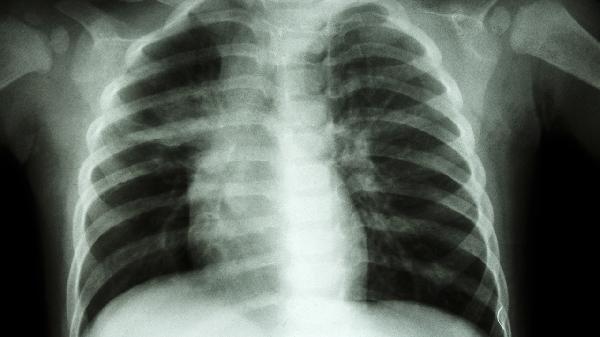

胸骨骨折多由外力撞击或挤压导致,如交通事故、高处坠落等。轻度骨折表现为局部疼痛、肿胀,深呼吸或咳嗽时加重,但胸廓结构保持稳定。此类患者可通过胸带固定限制活动,在疼痛耐受范围内逐步恢复日常活动,避免剧烈运动或负重。早期适度活动有助于预防肺部感染和肌肉萎缩,但需定期复查影像学确认愈合情况。

严重胸骨骨折可能出现骨折端移位、胸廓变形,甚至损伤后方的心脏、大血管或肺组织。这类患者需绝对卧床2-4周,保持平卧位减少骨折端移动,必要时采用镇痛药物如洛索洛芬钠片、塞来昔布胶囊缓解疼痛。合并血气胸者需行胸腔闭式引流术,严重移位骨折可能需手术内固定。卧床期间应每2小时协助翻身拍背,进行下肢踝泵运动预防血栓。